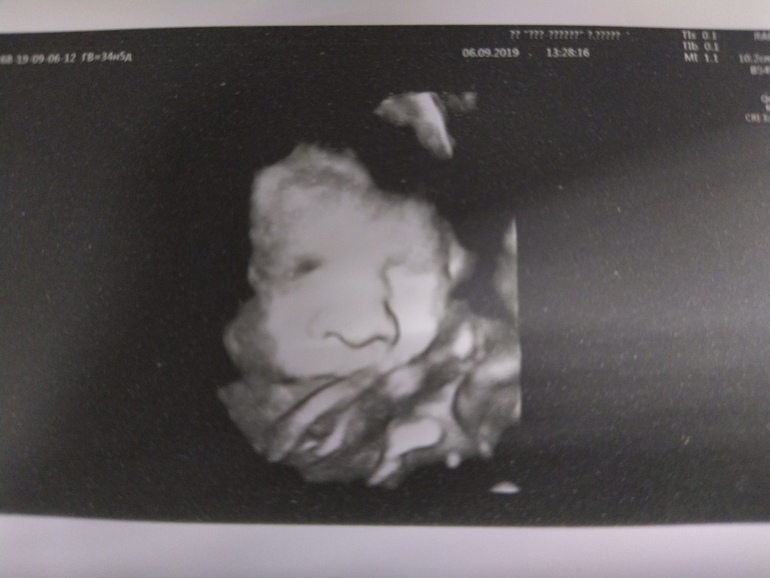

..Неделю назад была на узи (35н) Просто для себя на фотку влез только нос) Весили мы 2752. Пуповина есть на шее но не туго...

Ну ладно, главное малышка здорова и всё гуд! А теперь вы и встретитесь уже вот вот! )))) На узи видишь сейчас ничего не видно один нос)